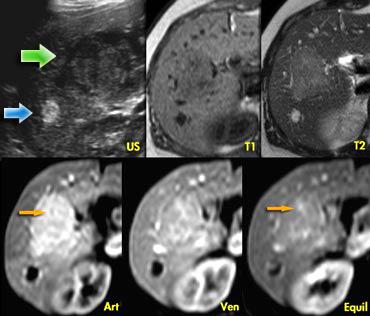

Hình ảnh siêu âm bên trái cho thấy hai tổn thương.

Tổn thương nhỏ (mũi tên xanh dương) có đặc điểm điển hình của u máu, trong khi tổn thương lớn hơn (mũi tên xanh lá) không đặc hiệu trên siêu âm.

Trên chuỗi xung T2W, u máu cho thấy tăng tín hiệu đồng nhất điển hình.

Tổn thương lớn hơn giảm tín hiệu nhẹ trên T1 và tăng tín hiệu nhẹ trên T2.

Ngấm thuốc gần như đồng nhất với các vách ngăn nhỏ không ngấm thuốc trong pha động mạch và có ngấm thuốc muộn (mũi tên vàng).

Chúng tôi cũng xếp loại tổn thương này là FNH.